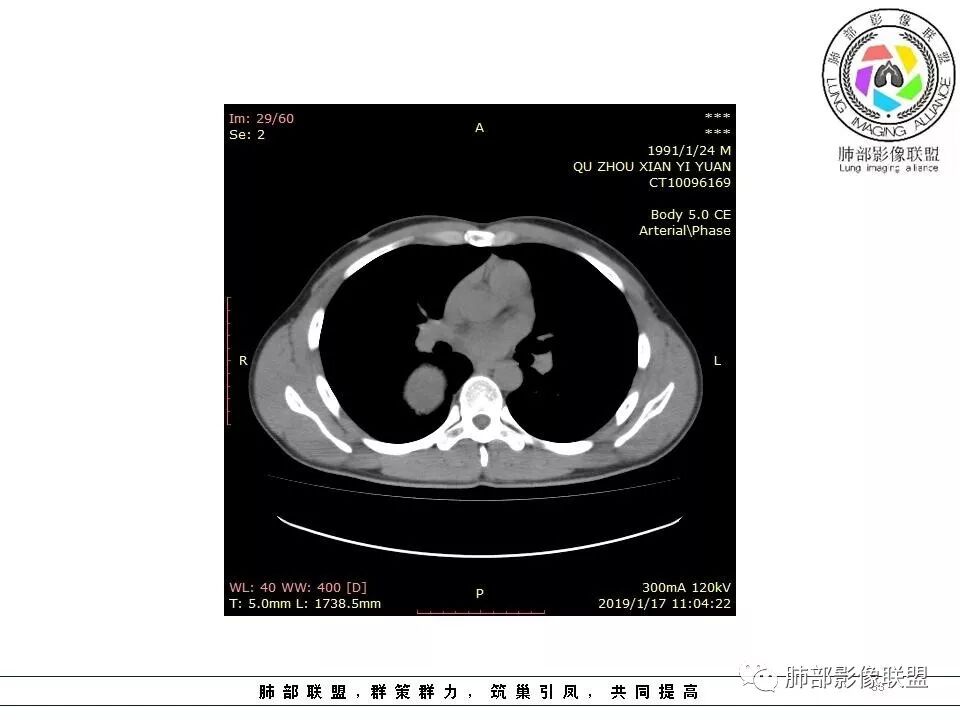

青年男性,间断胸痛;右侧脊柱旁可见一类圆形软组织密度影,密度欠均匀,增强扫描呈轻中度持续强化,邻近肺组织及肺动脉推移,可见肋间动脉供血,部分胸膜下脂肪可见,部分层面似见与右侧椎间孔相连。考虑后纵隔神经源性肿瘤。

青年男性,右侧脊柱旁软组织肿块,边缘膨隆,密度不均,临近肺组织受压、胸膜增厚,增强后动脉期呈不均匀强化,并可见肋间动脉供血,延迟期强化较均匀,定位肺外,首先考虑SFT,神经源性肿瘤待排

青年男性,右后上纵隔脊柱旁沟可见团状软组织影,边界清,密度尚均匀,推挤邻近肺组织,胸膜可见掀起,有肺动脉供血,增强轻度蛇皮样强化,纵隔淋巴结未见肿大,邻近骨质未见破坏,胸膜下脂肪间隙消失,考虑SFT孤立性纤维瘤可能性大,鉴别神经鞘瘤,节细胞瘤,建议活检。

青年男性,胸痛,右上纵膈脊柱旁肿块,形态光整规则,支气管被推移,临近的胸膜明显增厚,有胸膜掀起,增强后密度不均匀,可见蛇形血管征,血供似乎有两根血管供血,考虑SFT

年轻患者,偶胸痛,巨大肿块,无明显纵膈淋巴结肿大,无明显胸腔积液,考虑良性或低度恶性肿瘤。30.8-44-58-61hu,渐进性强化,边缘光滑,平扫密度不均,增强密度不均,纤维可以渐进性强化,不强化(或低密度去)区,为粘液。考虑孤立性纤维腺瘤伴粘液。

或者是某种肿瘤的坏死,但坏死不明显,低密度区呈湖泊样,巨淋巴结增生,与性质有关。

血管贴边征,邻近血管未明显增粗,体循环可能,其内血管未破坏,血供丰富,不除外血管源性。

青年男性,右侧脊柱旁占位,瘤肺界限清晰,支气管推移,胸膜尾,D字征,胸膜下脂肪影,蛇纹血管,双重供血,延迟强化,定位胸膜,支持sft

边缘光滑,宽基底与胸壁相连,跨叶裂,叶裂稍前推,血管、支气管前移。

浅分叶

肋间动脉供血,强化尚均匀,逐步强化

1.右上胸内脊柱旁类圆形肿块,质地似乎比较坚实,密度稍显不均,但未显示明确的坏死。

如此密度形态的病灶位于肺边缘首先应当想到孤立性纤维瘤,可相邻胸膜未见明显的异常强化和胸膜方向延伸。

2.肋间动脉病供血也提示肿块来自后纵隔?

3.相邻椎间孔未见扩大,也未见块影延入椎管,易起自于神经根的鞘瘤似乎找不到支持点。

4.静脉期轻度不均匀强化,注意不是环形强化,亦未见明确的“AB区”,这点也不支持神经鞘瘤。临床及病灶轻度强化都不支持副节瘤。

尽管神经纤维瘤的诊断确实有些出乎意外,但病例开阔了我们的视野。